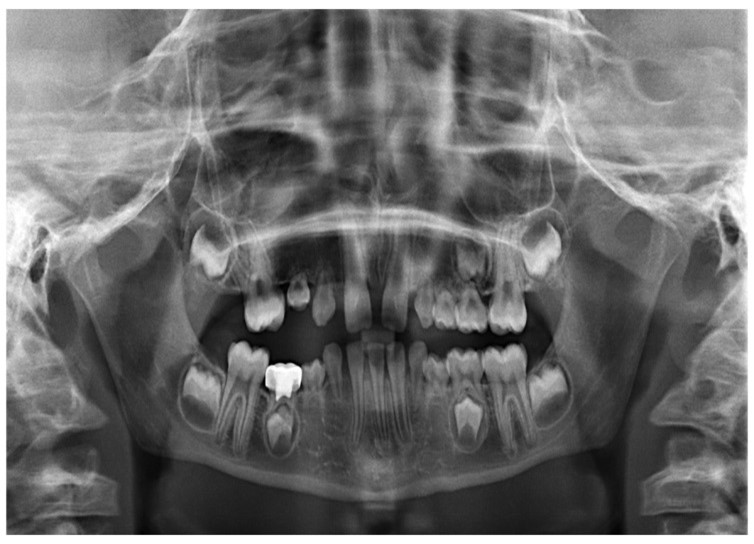

This condition, also known as brittle bone syndrome, is another example of a diverse collection of genetic disorders that are characterized by bones that are prone to bending and breaking readily. A common symptom of the condition is a delay in the healing of wounds, as well as a rotated and twisted spine, which can give the appearance of having a "humped-back" (kyphotic). Osteogenesis imperfecta tarda is the medical term for type I osteogenesis imperfecta. The sickness is the result of a reduction in the formation of 1 and 2 chains. Fractures that are the result of mild trauma appear in early childhood. A diagnosis of this condition can be made using prenatal ultrasound imaging that reveals bowing of the long bones or fractures. The most severe form of osteogenesis imperfecta is type II, also known as osteogenesis imperfecta congenita. Patients with pulmonary hypoplasia don't make it past the uterine or newborn stages of the disease. The majority of people who suffer from severe OI have mutations in the gene that codes for either the pro-1 or pro-2 chains of type I collagen. The majority of mutations result in the substitution of amino acids with bulky side chains for glycine residues (in the form –Gly–X–Y–). The structurally aberrant pro- chains that develop as a result of this process hinder the creation of the necessary triple-helical conformation.<br /><br />By: Asst. Lec. Ahmed B. Mahdi